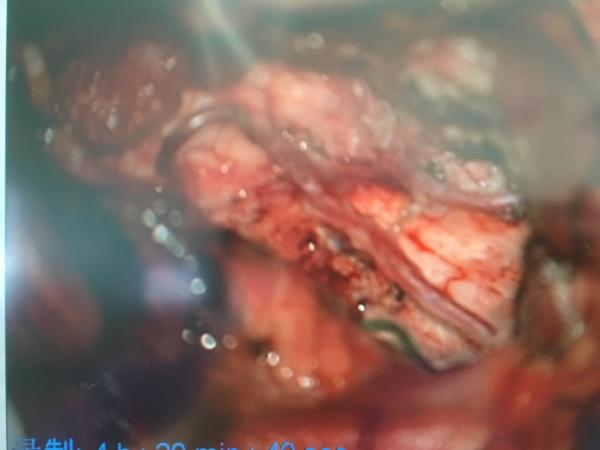

果然如我们术前预料,两侧的小脑后下动脉完整包绕在肿瘤组织之中,以超声刀和吸引器小心分离(见上图中两根迂曲的动脉),分离完整后才是最困难的,我们需要在两根迂曲血管的间隙中继续向下分离至脑干(延髓),万幸!肿瘤与延髓表面有明确的分界,所以考虑室管膜瘤可能大,而术中的冰冻也证明了我们的想法.